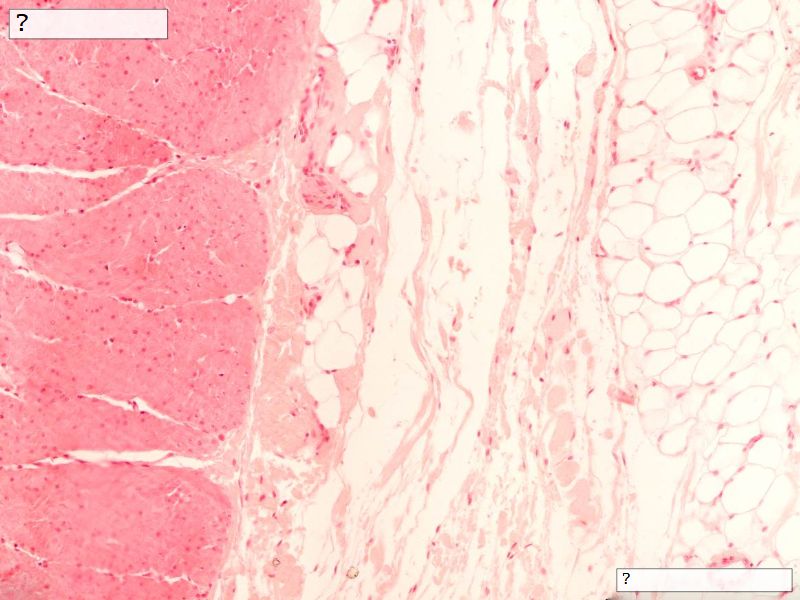

Fill in all the missing labels, and assess as you move through the slides. Answers on the down slide. It is important to do this using pen and paper, and not just glance through the images.